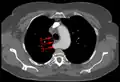

L'artère sous-clavière aberrante, ou artera lusoria, est une rare variante anatomique de l'origine de l'artère sous-clavière droite. Cette anomalie vasculaire congénitale est l'anomalie la plus courante de l'arc aortique[2], survenant chez environ 1 % des individus[2]. Au lieu de naître de la division du tronc artériel brachio-céphalique, l'artère sous-clavière droite naît alors directement de la crosse aortique. Elle possède un trajet rétro-œsophagien pouvant être source de dysphagie.

Artère sous-clavière aberrante au scanner axial. (1) trachée, (2) œsophage, (3) Artère sous-clavière aberrante.- Artère sous-clavière droite aberrante à l'angiographie.